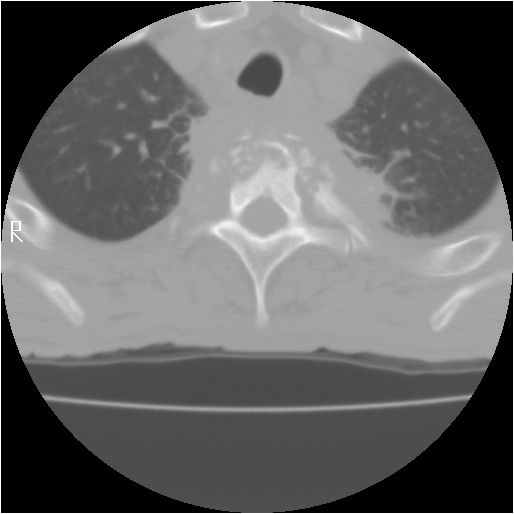

The thoracic spine can be approached through the right or left chest and communication with the spine surgeon is mandatory so that the approach and extent of exposure can be tailored appropriately. In the absence of lateralizing pathology, either a right or left-sided thoracotomy can be used to expose the thoracic spine. As a general rule, the upper thoracic spine (T2-9) is better approached from the right side because of the location of the heart, aortic arch and great vessels. Conversely, in the case of the thoracolumbar spine (T10-L2) a left-sided thoracotomy is preferred to avoid liver retraction. The side of approach must provide maximum exposure to the pathology to be treated. Local factors such as previous thoracotomy, pleurodesis, or infection should also be considered. In general, a right sided approach provides more direct access to the spine, as the mediastinal structures lie to the left of the vertebral bodies. CT and MRI allow for a precise evaluation of the anatomy of the spine pathology and the related intra-thoracic structures (Figures 1a, 1b).